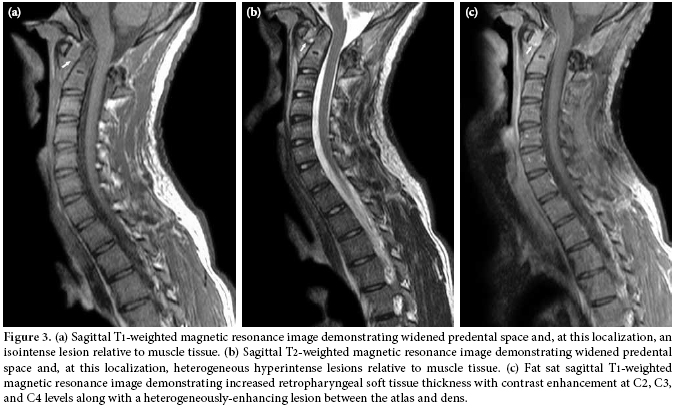

The lateral view of the cervical radiography revealed atlantoaxial subluxation (figure 1). On the computed tomography (CT), the distance between the axis and dens clearly widened as it measured approximately 10 mm (figure 2). The T1-weighted magnetic resonance imaging (MRI) showed a widened atlantodental space (figure 3a). At this localization, T2-weighted images revealed a heterogeneous hyperintense lesion, and at C2, C3, and C4 levels increased retropharyngeal soft tissue thickness appeared (figure 3b). In postcontrast T1-weighted sequences, the increased retropharyngeal soft tissue thickness and lesion showed heterogenous enhancement which was interpreted as soft tissue infection and abscess, respectively (figure 3c).

Radiological investigation plays an important role in the diagnosis. Plain anteroposterior and lateral radiographs may show asymmetry of the facet joints and increased predental space.[8] Both CT scanning and MRI are diagnostically used.[10] In our case, retropharyngeal soft tissue swelling was demonstrated. Dynamic studies may be necessary, but they may cause neurological complications.[14]